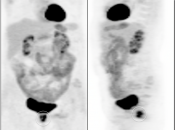

- Assess Response to Therapy

Assessing Response to Therapy:

- Early Response: Non-responders can be offered alternative therapy.

- Late Response: Assess success or failure of therapy, and ultimate outcome.

Recurrence & Restaging: (Most common indication)

- Rising tumor markers & negative (or indeterminate) CT scan.

- Restaging known recurrence, especially if surgery is contemplated.

- Distinguishing recurrence from post-therapeutic inflammation/scarring.